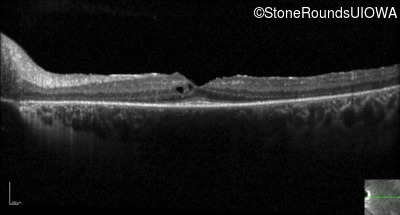

Optical Coherence Tomography - Right -

20/20 -1

Exemplar / OCT Stack

Optical Coherence Tomography - Left -

20/20 -2